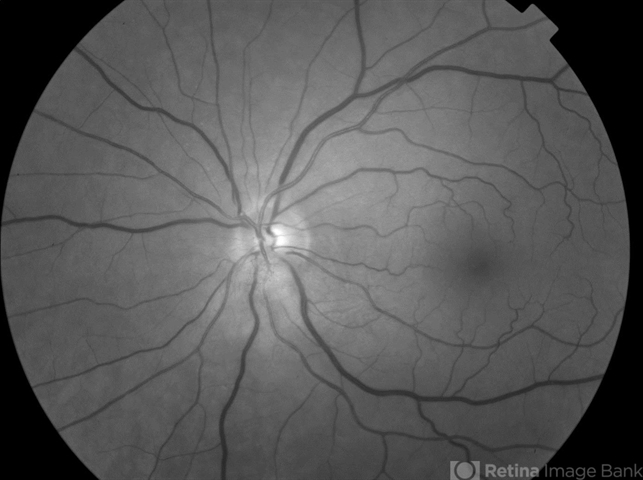

- Solitary NonSyndromatic Astrocytic Hemartoma of the Retina

- astrocytic hamartoma

- Maisee Yang

- Fundus camera

- 66-year-old white male without history of tuberous sclerosis was found to have an incidental, asymptomatic, translucent, retinal lesion with a few small telangiectatic vessels within it. The FA showed early hyperFL of these small vessels with prominent late leakage/staining. The OCT showed a retinal mass with a "moth eaten" appearance. Vision was 20/20 and the rest of the exam was unremarkable.